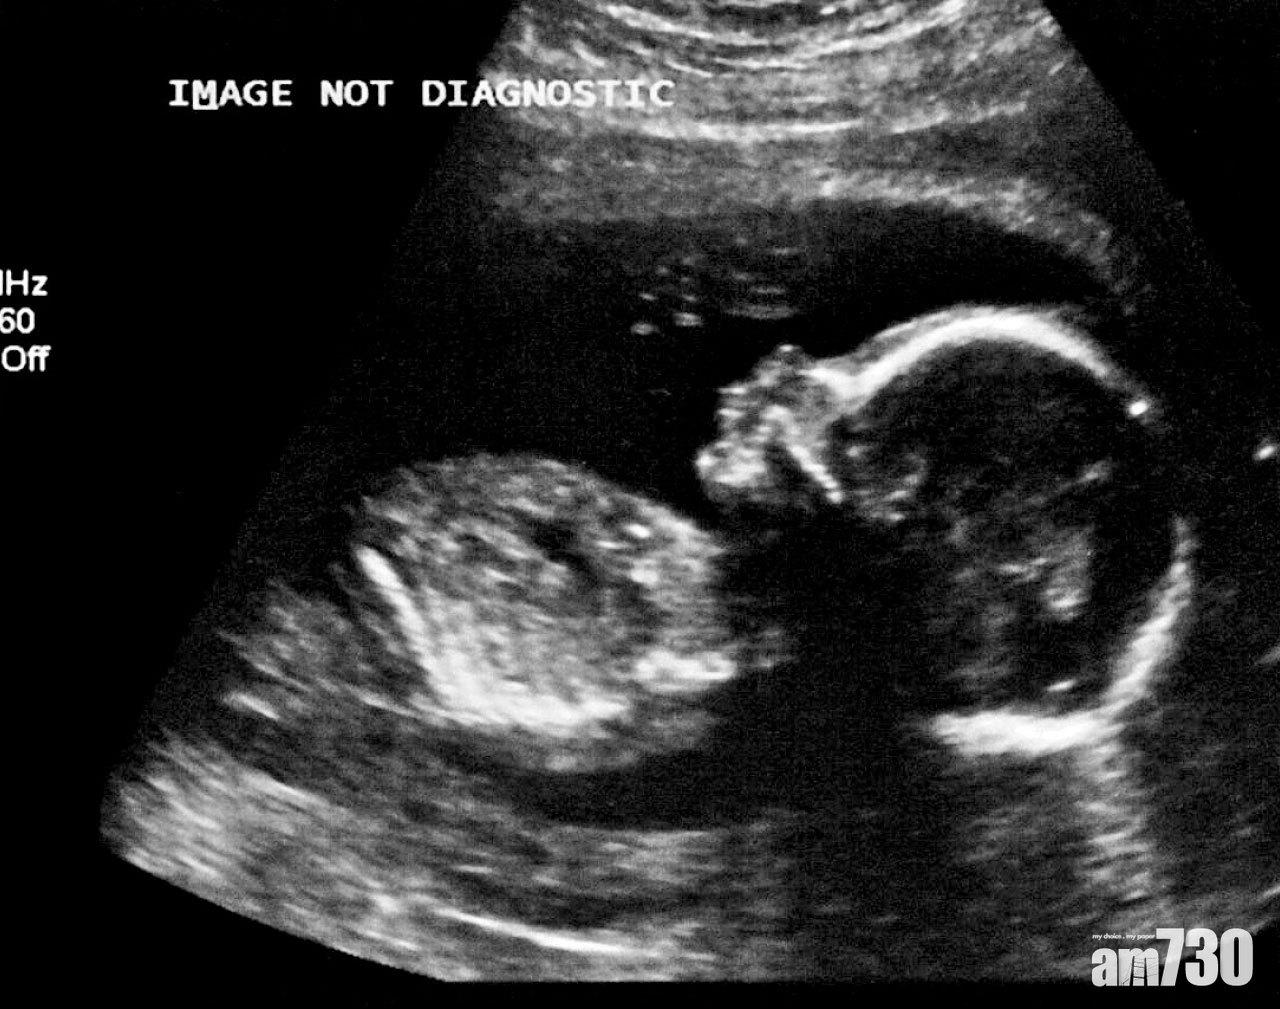

日本有嬰兒疑經母體染疫。(資料圖片)

日本醫學團體調查發現,新冠肺炎疫情爆發以來,截至去年8月底,最少52名確診孕婦誕下嬰兒,其中一名初生嬰兒病毒檢測呈陽性,可能經母體感染,是該國首例。

NHK周一報道,日本兒科學會等團體對國內設有兒科的1,124間醫療機構做問卷調查,發現其中31間有確診孕婦分娩,共誕下52名嬰兒,其中1名嬰兒出生後病毒檢測呈陽性,另外51人均陰性。確診嬰兒健康良好,疑經母體受感染,其他國家早有類似個案。專家指,孕婦傳染新冠病毒給胎兒的可能性很低,嬰兒症狀輕微,民眾毋須太擔心。